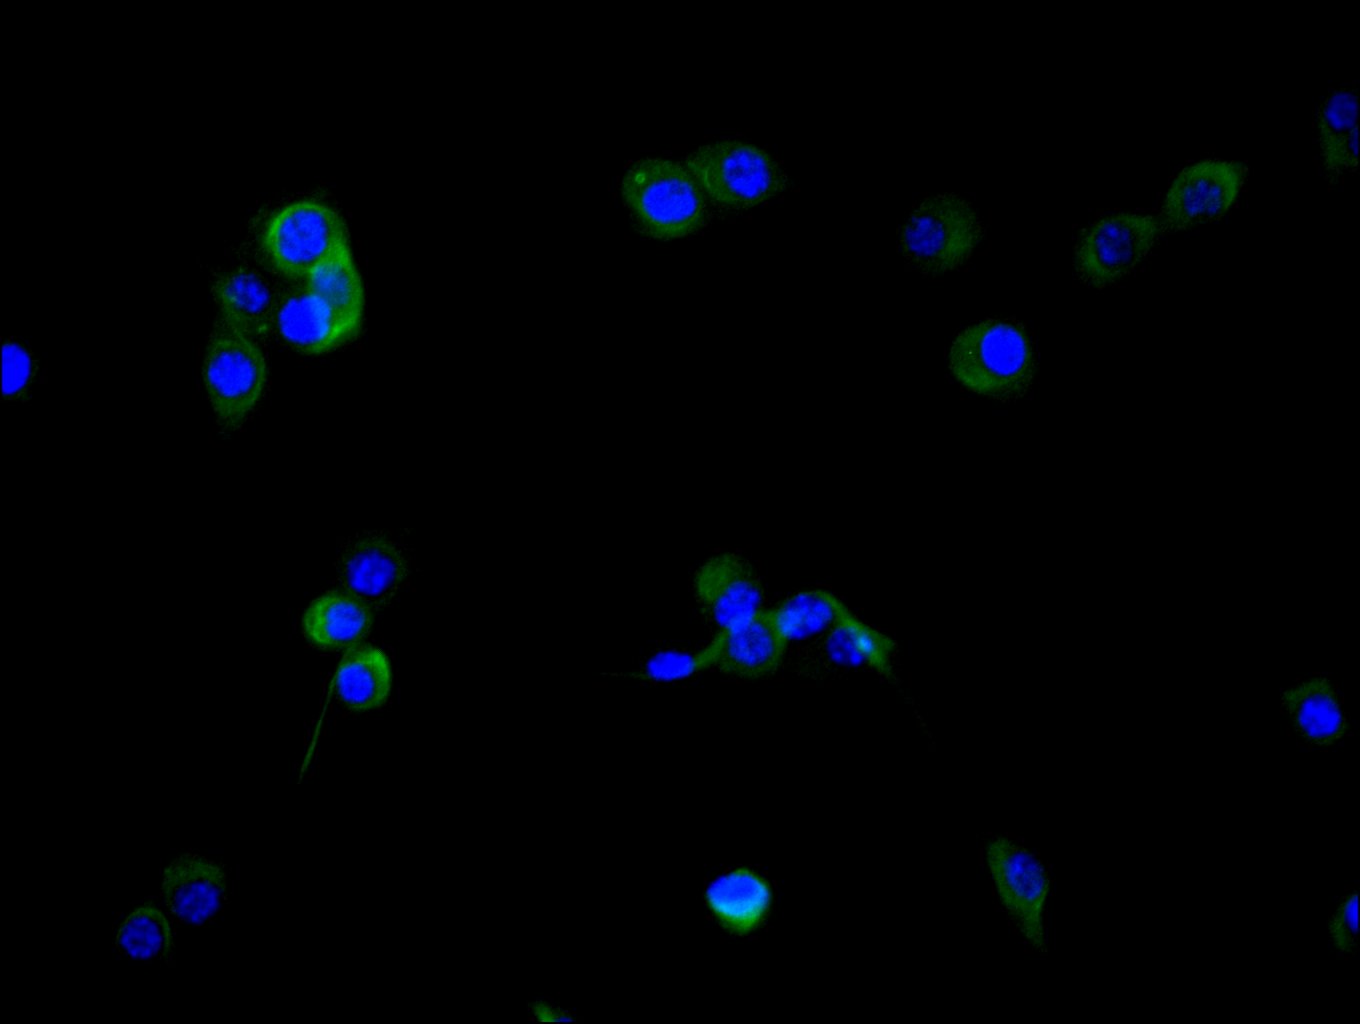

● FAP抗體

FAP Recombinant Monoclonal Antibody; CSB-RA008424MA1HU

FAP Recombinant Monoclonal Antibody; CSB-RA008424MA2HU